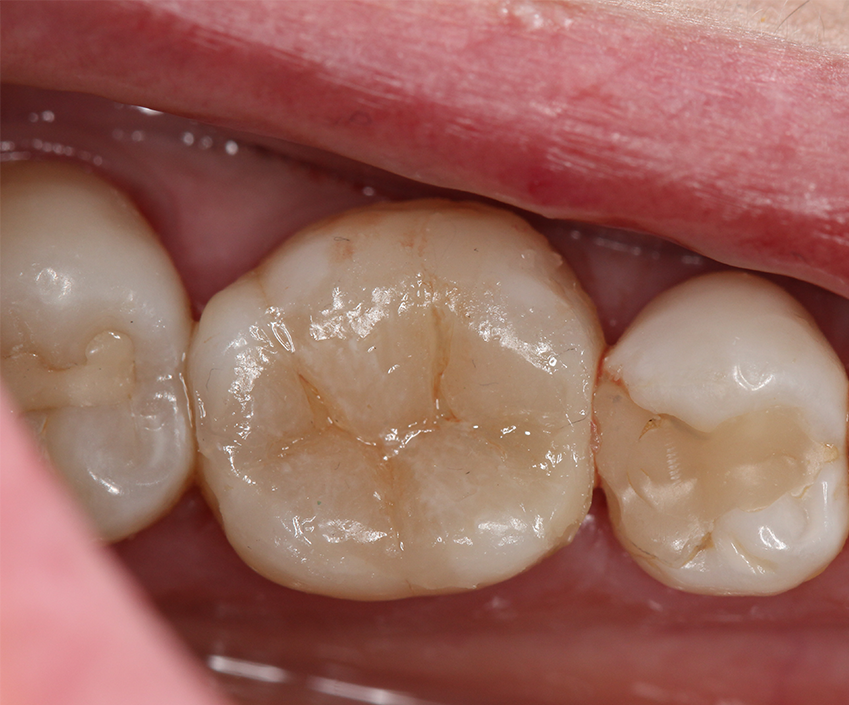

The restorative procedure continued by filling the cavity to the occlusal cavosurface margin with a single layer (Fig. 9) of a regular consistency bulk fill composite (Tetric EvoCeram Bulk Fill). Stain was added to enhance the occlusal pits delimitations and optically give depth to the final restoration (Fig. 10), followed by the application of an enamel bonding agent (Heliobond, Ivoclar Vivadent) to serve as a fissure sealant and prevent abrasion and leaching of the pigments. Each step was followed by light-curing (Bluephase 20i), and a final light-curing protocol was performed with glycerin gel in order to polymerize the composite oxygen-inhibition layer. Final aspect of the restoration was evaluated after removal of the rubber dam (Fig. 11).

Fig. 9 Fig. 10

Final occlusion was checked, followed by finishing and polishing (Astropol, Ivoclar Vivadent). The restoration was once again checked for function and esthetic.